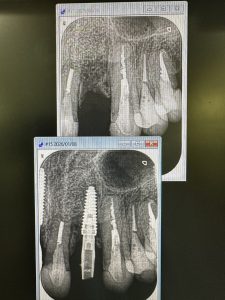

朝から今年初インプラントオペ

難なく30分で終わり、仮歯まで!

80〰️90Nで初期固定